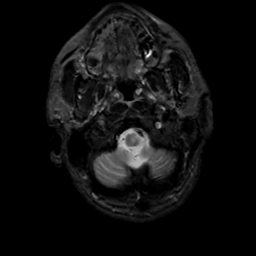

MR Study #5, March 10, 1991 -- Slice #5